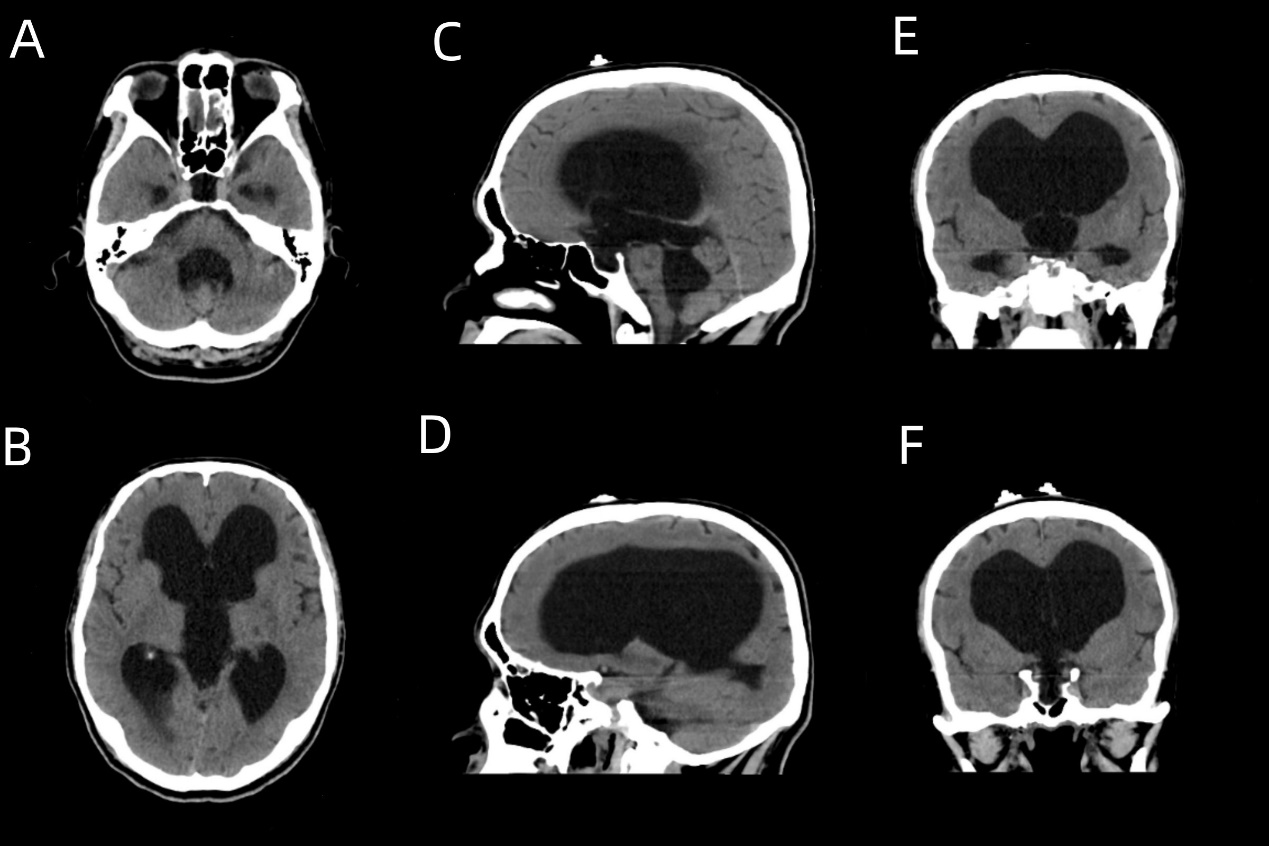

北院神经外科夏广文主任仔细询问病史并结合体格检查后觉得这一切很可能是脑积水引起的,随即为其完善颅脑CT检查。检查可见:第三脑室、第四脑室、中脑导水管及双侧侧脑室明显扩张,双侧侧脑室旁白质密度降低。